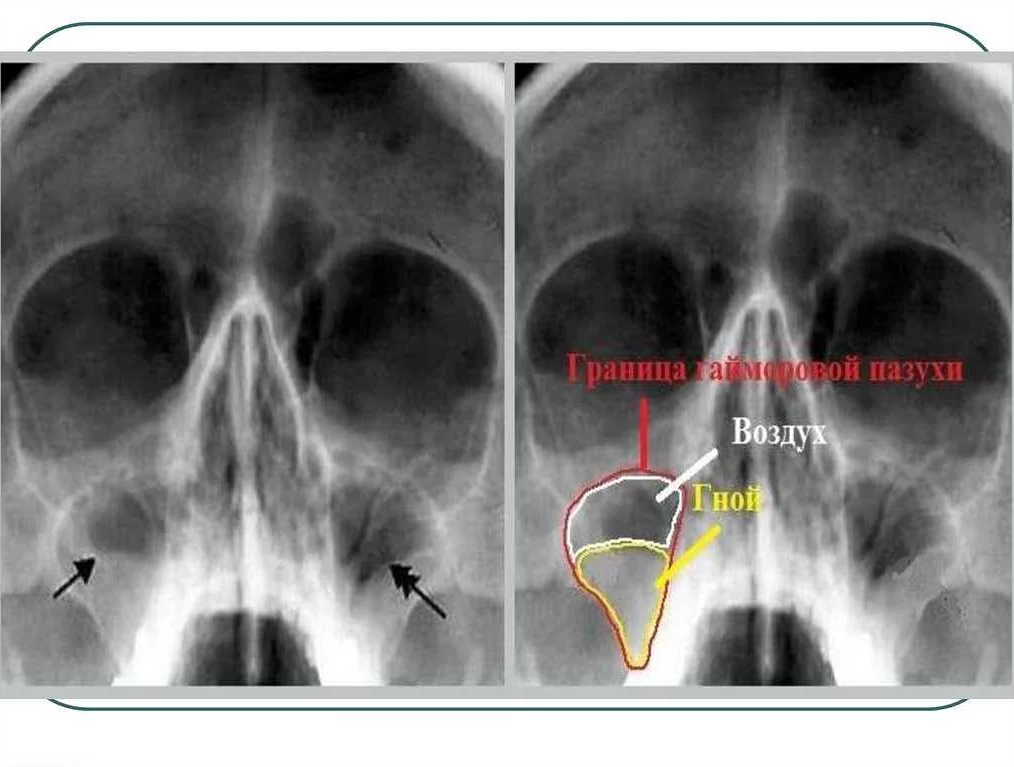

Для постановления диагноза используют риноскопию, в ходе которой специалист может обнаружить отечность слизистых оболочек, бледность определенных участков, повреждение сосудов. Если присутствуют симптомы, характерные для хронического гайморита, необходим рентген носовых пазух. Только на рентгеновских снимках можно заметить начальные стадии образований и пристеночный отек.